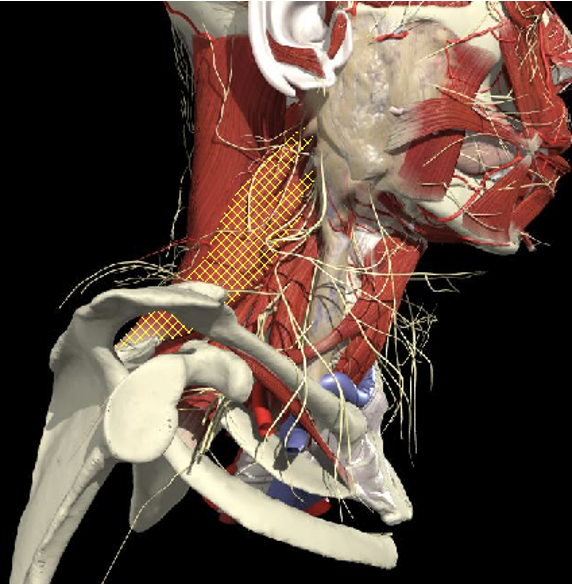

Structures to Avoid

Arteries

- Carotid artery

Midpoint anterior border of SCM

Vertebral artery

- Occipital bone or C2 towards midline is safe

Occipital artery

Avoid apex of posterior triangle

Window between arch of C1 , superior oblique and rectus major

OCS

RC

C2

OCI

Transverse Process - C1

Arch of C1

Landmarks